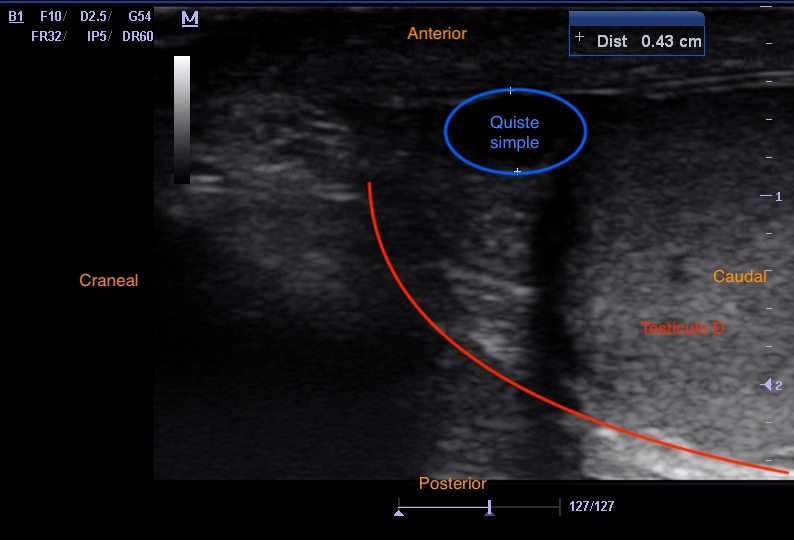

Se observa una imagen hiperecoica en 1/3 medio pared anterior de testículo derecho compatible con calcificación que deja sombra posterior, bien delimitada y sin imagen adyacente hipoecoica ni heterogénea. Además, se observa imagen en panal de abeja en epidídimo, que sugiere ectasia tubular de rete testis.

Ectasia tubular de rete testis y calcificación inespecífica de testículo derecho.